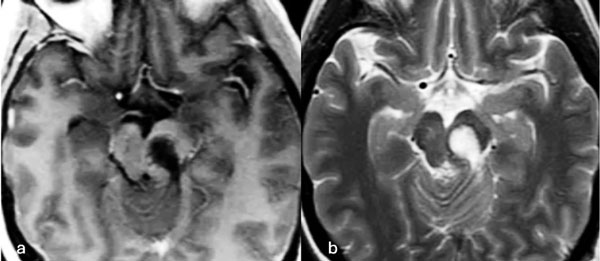

Caso 1: cavernoma mesencefálico

Una mujer de 35 años debutó con un cuadro de cefalea asociada a diplopía por parálisis del tercer par craneal izquierdo y hemihipoestesia del hemicuerpo derecho. La RM de encéfalo evidenció una malformación cavernomatosa tegmental izquierda con signos de sangrado reciente. Un año después del sangrado, la paciente fue sometida a una exéresis de la lesión mediante un abordaje suboccipital lateral y supracerebeloso infratentorial izquierdo (Figura 1), logrando una exéresis completa de la malformación (Figura 2). Después del procedimiento, la paciente no presentó nuevos déficits agregados.

Figura 1. Imágenes intraoperatorias bajo microscopía. Craneotomía suboccipital lateral. Se ingresa al mesencéfalo desde posterior por una ruta supracerebelosa infratentorial lateral. A y B) Corticotomía en surco mesencéfalo lateral. C) Identificación y resección en bloque de la malformación cavernomatosa. D) Revisión del lecho, sin remanente.

Figura 2. RM postquirúrgica de encéfalo. Se evidencia una exéresis completa, sin lesión de estructuras adyacentes. A) Imagen ponderada en T1 posterior a la administración de gadolinio, corte axial. B) Imagen ponderada en T2, corte axial.